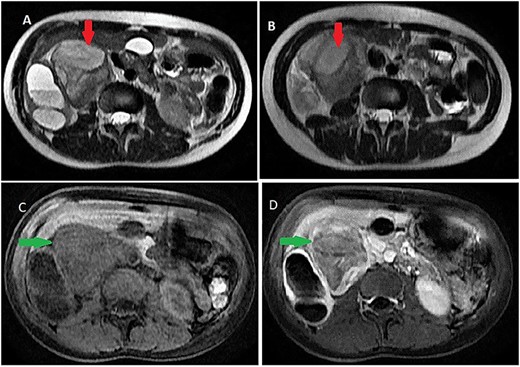

It was abutting the abdominal aorta, inferior vena cava and right renal pedicle. It extended toward the liver and right diaphragmatic pillar. It was compressing the kidney and ureter with ureterohydronephrosis and cortical thinning. Renal calyces and pelvis contents were dense and their walls enhanced (Fig. 3). The adrenal gland was normal.

Ureterohydronephrosis due to the mass effect; ureterohydronephrosis (green arrow) due to the mass effect (red spark) on coronal (A), sagittal (B) Ct scan and coronal MRI T2-weighted image (C and D).